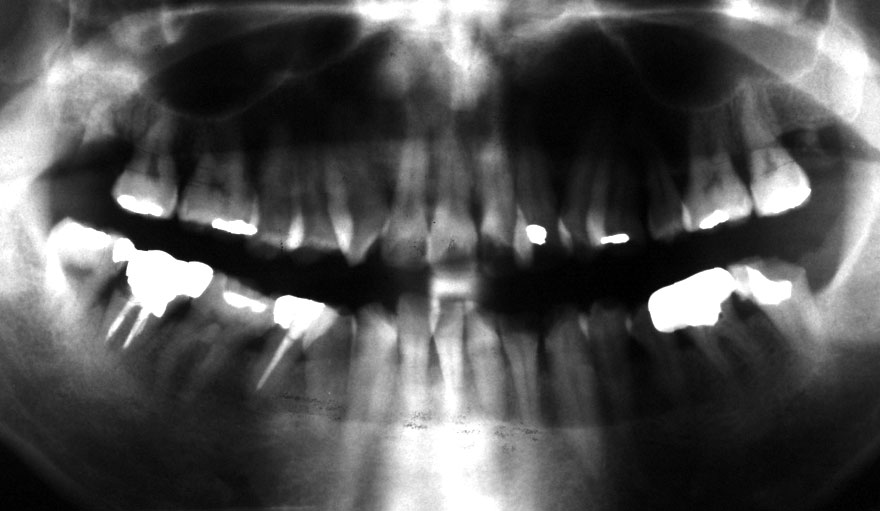

初診時 38歳 男性 平均歯槽骨喪失量:6.520mm

25年後 63歳

平均歯槽骨喪失量:8.57mm

25年間喪失量:-2.05mm

年間喪失速度:-0.08mm

(ケア頻度:1.38ヵ月ごと)